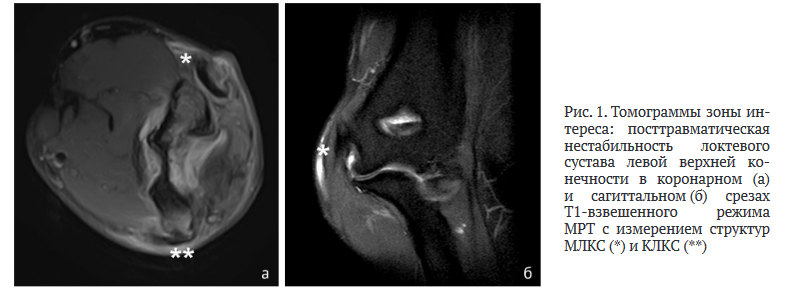

Морфометрия: сгиба- ние/разгибание — 55/160°, пронация/супинация — 80/45°. Оценка силы механическим динамометром: Dex. 90; Sin. 65 (2daN). Учитывая противоречие адресных клинических тестов, выполнено инструментальное исследование в объеме МРТ 1,5 Тл локтевого сустава с выявлением повреждения области «анатомического оттиска» МЛКС/КЛКС (рис. 1). Дополнительно визуализированы дефект суставной поверхностности trochlea humeri и fossa olecrani, интралигаментарная оссификация МЛКС с провокацией кортикального слоя медиального надмыщелка левой плечевой кости и КЛКС, экзостоз олекранона локтевой кости.